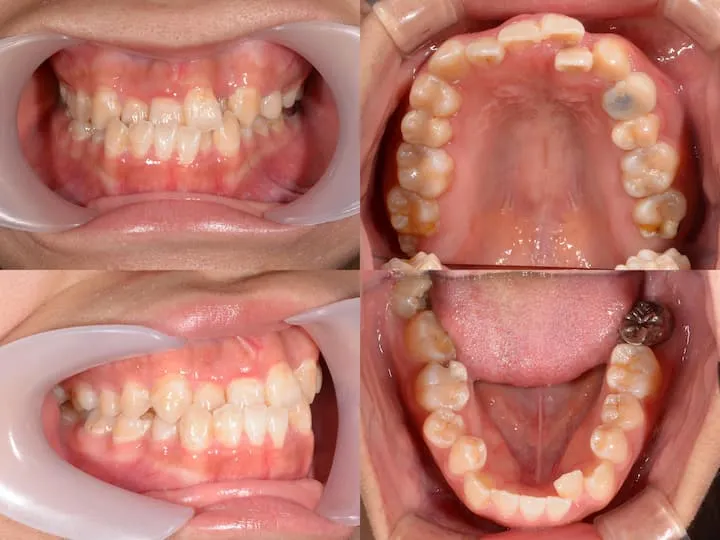

治療例

治療方法

初診時年齢20歳9ヶ月の患者様です。前歯のガタつきと受け口を主訴にご来院されました。大臼歯関係がIII級 (下顎大臼歯近心位) だったため、下顎左右8番を抜歯して顎間ゴムで下顎大臼歯を遠心移動しました。

遠心移動量が足りない場合にはアンカースクリューを用いる予定でしたが、8番抜歯直後に治療を開始したことと、顎間ゴムを長時間使っていただけたため、本症例ではアンカースクリューなしで下顎大臼歯の遠心移動を必要量行うことができました。

| 使用装置 | ハーフリンガル |

|---|---|

| 治療期間 | 1年1ヶ月 |

| 通院頻度 | 1ヶ月に1回 |

| 費用 | 総額 129万6千円 (税込) ※分割払い可 (月々13,245円より) |